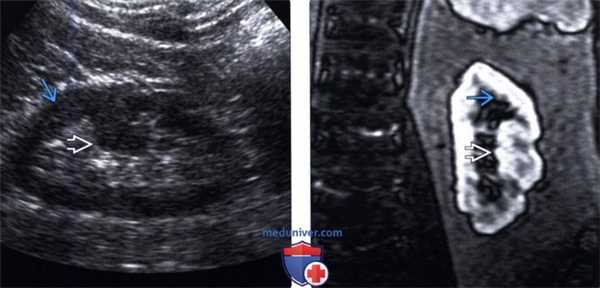

(Левый) Продольный ультразвуковой срез правой почки, визуализируется гипертрофирован ная бертиниева колонна, изоэхогенная корковому веществу почки.

(Правый) МРТ с контрастным усилением у этого же пациента (по поводу другого заболевания почки; не показано), визуализируется очаг такой же интенсивности сигнала, как и корковое вещество почки, сравнимое с гипертрофированной бертиниевой колонной.